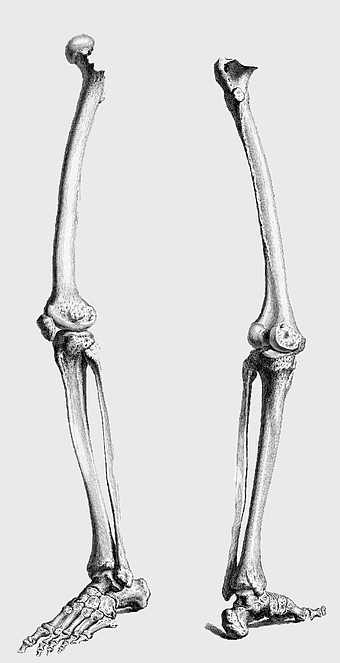

Human leg skeleton, femur anatomy, monochrome drawing, tibia and fibula, skeletal limb illustration, medical bone diagram, lower extremity structure -